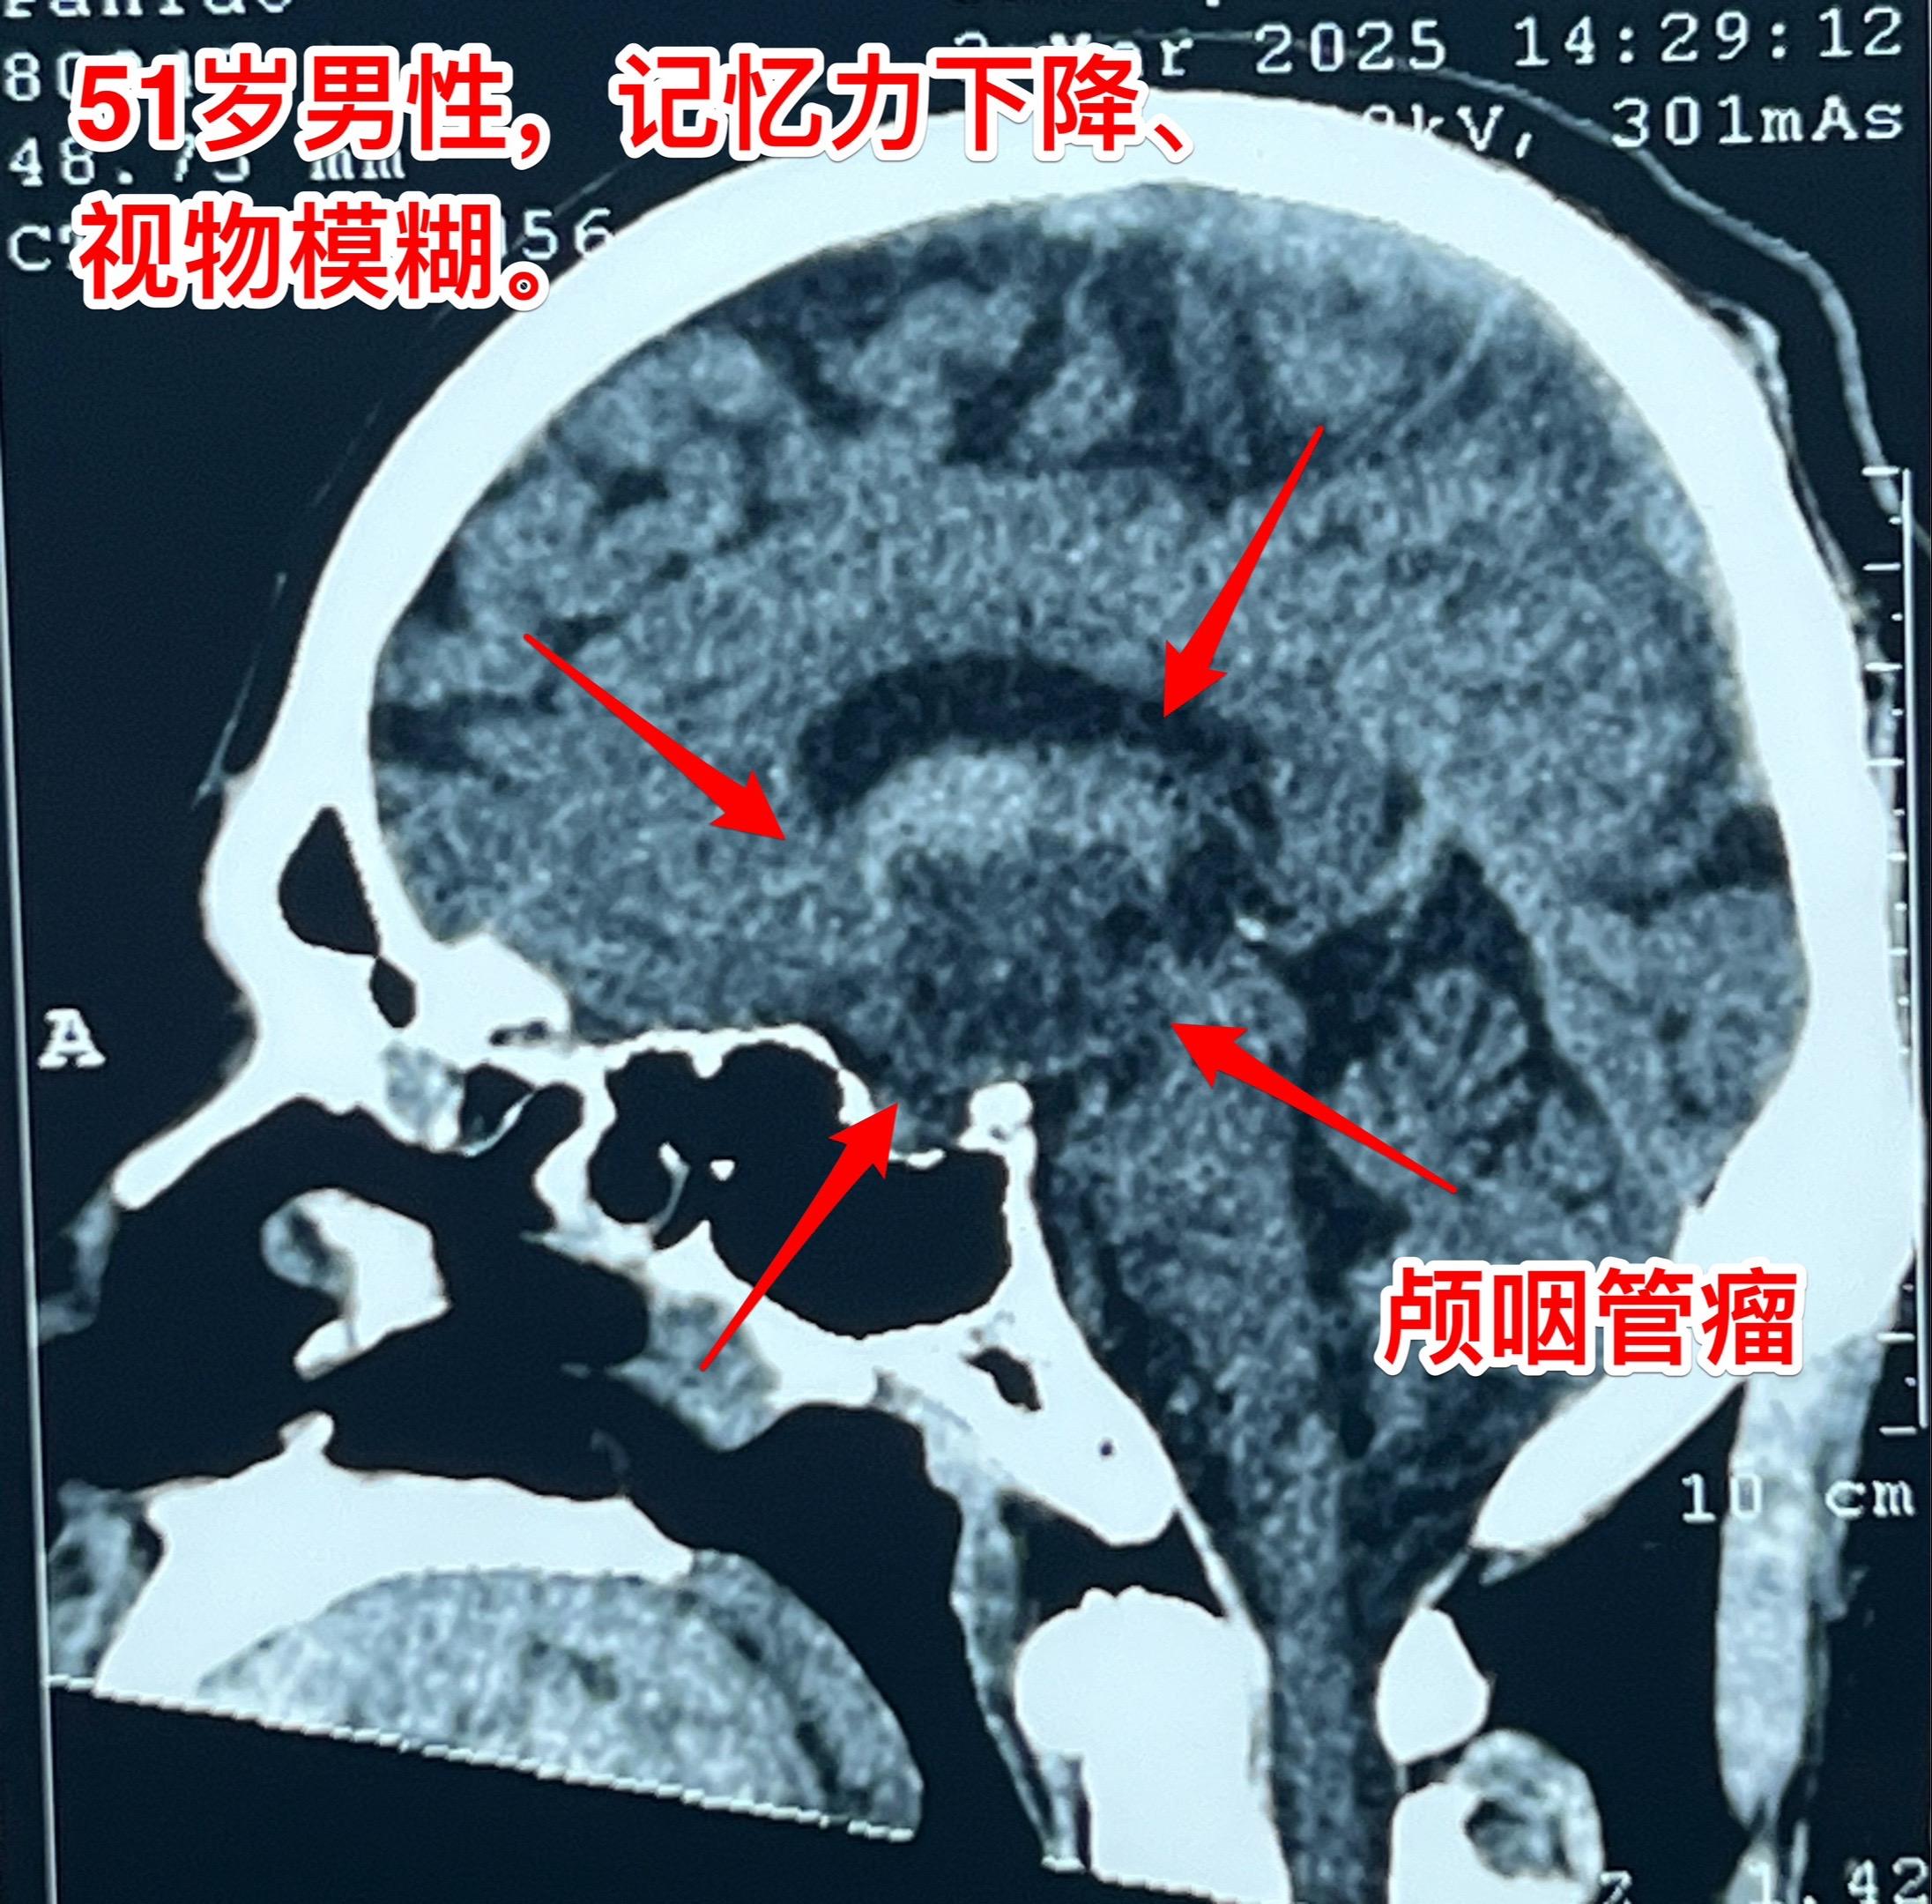

昨日一个颅咽管瘤手术+一个胶质瘤手术。昨日第一个手术:51岁男性,卡车...

2025-03-16 11:25